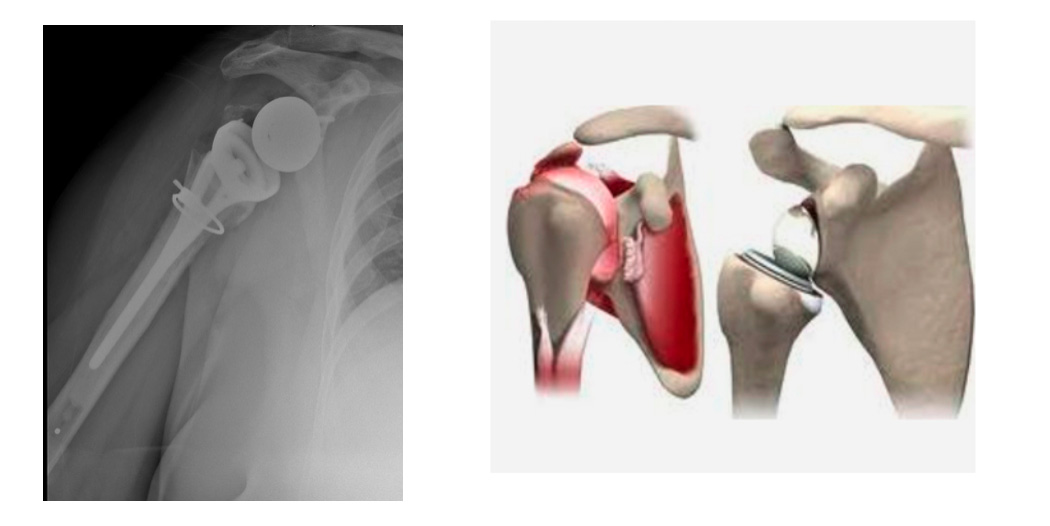

3. Ters Omuz Protezi

Geniş ve onarılamayan rotator manşet yırtıkları, çok parçalı omuz kırıkları veya başarısız protez revizyonlarında kullanılır. Protez, anatomik yapının tersine yerleştirilir: topuz kısmı yuvaya, yuva kısmı topuz haline getirilir. Çıkık riski düşüktür ve ileri yaş hastalarda fonksiyonel sonuçları oldukça iyidir.

Kaynak: Grammont P, et al. *Clin Orthop Relat Res.* 1991 – Ters protezler, manşet yırtığı artropatisinde altın standarttır.

Total omuz protezi ile ters (reverse) omuz protezi farkı nedir?

Ters omuz protezi: Topuz ve yuva yer değiştirir. Özellikle kas yetersizliği, onarılamayan rotator manşet yırtıkları veya çok parçalı omuz kırıkları olan hastalarda uygulanır.